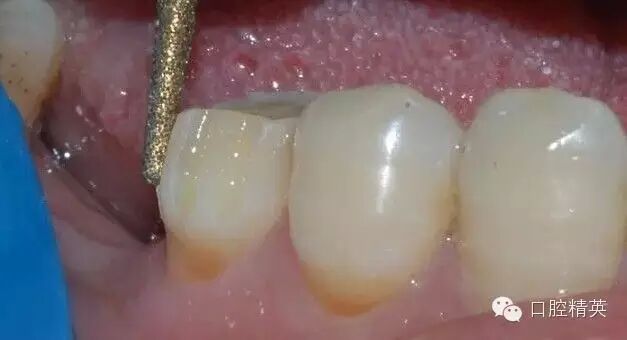

鎢鋼車(chē)針拋光修整

鎢鋼陳針拋光后的